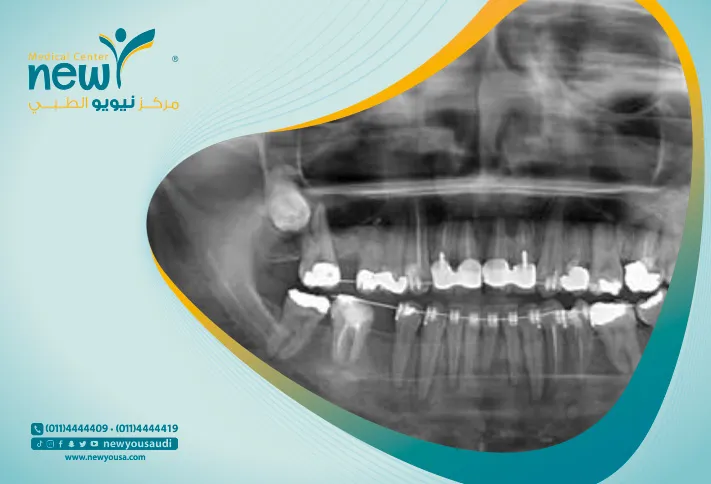

على عكس هذا التصوير الشعاعي التقليدي ، فإن اشعة بانوراما اسنان تخلق صورة واحدة للفم بأكمله: الفكين العلوي والسفلي ، مفصل الفك الصدغي(TMJ) ، وجميع الأسنان ومنطقة الأنف والجيوب الأنفية. توفر هذه الصورة تمثيلاً مسطحًا للهيكل المنحني للفك ، مما يسهل تحليل كل جزء بالاضافة الى انخفاض اسعار اشعة بانوراما اسنان مقارنة بتصوير كل جانب على حدى.

التصوير الشعاعي البانورامي ، الذي يُطلق عليه أيضًا اشعة بانوراما اسنان ، هو فحص بالأشعة السينية ثنائي الأبعاد (2-D) للأسنان يلتقط الفم بالكامل في صورة واحدة ، بما في ذلك الأسنان و الفكين العلوي والسفلي والتركيبات والأنسجة المحيطة.

الفك عبارة عن هيكل منحني يشبه حدوة الحصان. ومع ذلك ، فإن أشعة الأسنان البانوراما تنتج صورة مسطحة للبنية المنحنية. عادة ما تعطي الصورة البانورامية تفاصيل عن العظام والأسنان.

اشعة الاسنان البانوراما هي فحص يتم إجراؤه بشكل شائع من قبل أطباء الأسنان وجراحة الفم في الممارسة اليومية وهي أداة تشخيصية مهمة علاوه على انخفاض اسعار اشعة بانوراما اسنان.  يغطي مساحة أوسع من الأشعة السينية التقليدية داخل الفم ، ونتيجة لذلك ، يوفر معلومات قيمة عن الجيوب الأنفية الفكية ووضع الأسنان وغيرها من تشوهات العظام. يستخدم هذا الفحص أيضًا لتخطيط العلاج لأطقم الأسنان الكاملة والجزئية وتقويم الأسنان وخلع وزراعة الأسنان.